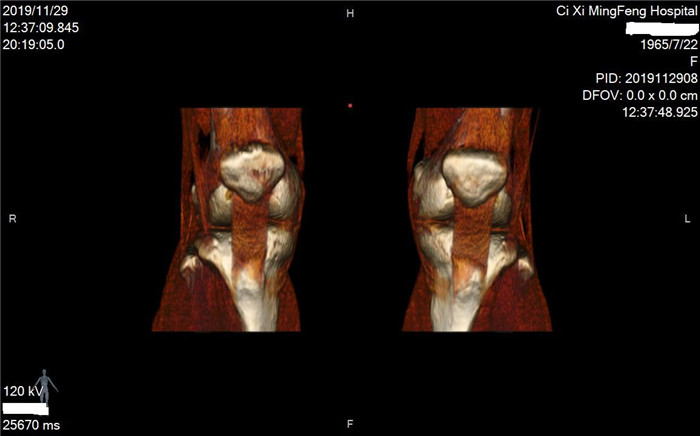

明峰CT搭載了領(lǐng)先的硬件技術(shù)平臺(tái)及系統(tǒng),強(qiáng)大的掃描能力可滿(mǎn)足臨床的各種要求,呈現(xiàn)更極致的細(xì)節(jié),為各臨床科室提供高品質(zhì)的圖像。薄層掃描,消除部分容積效應(yīng),提高各向同性。配合高分辨率算法,有助于細(xì)微結(jié)構(gòu)和形態(tài)學(xué)顯示。